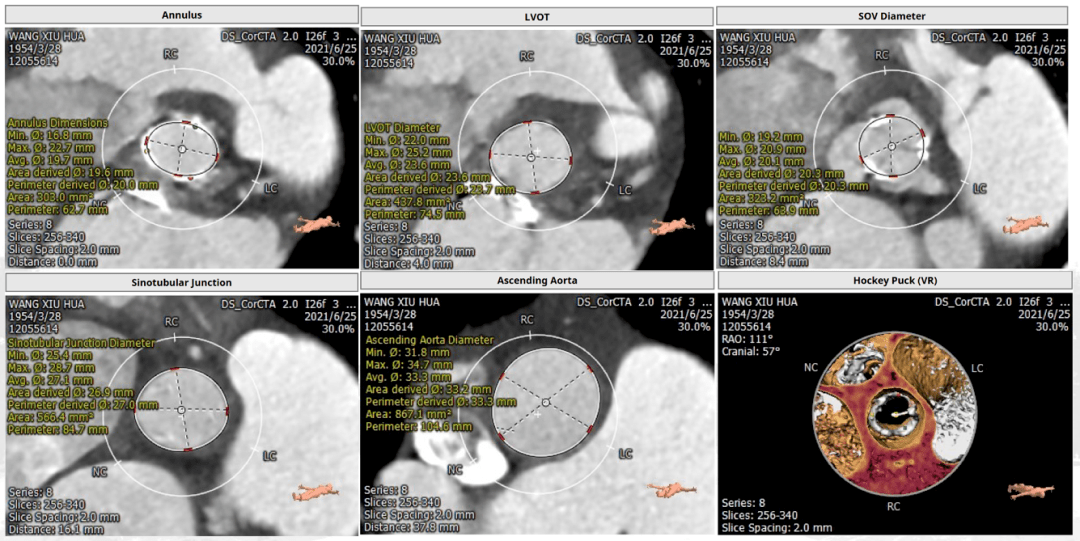

阜外首例二尖瓣与主动脉瓣生物瓣损毁·同期经导管双瓣置换